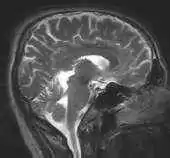

روشهای تشخیص زنده ، آن روشهایی هستند که در آنها یک رادیودارو در سیستم یک مریض زنده بطریق خوراندن ، تزریق یا با استنشاق وارد میگردد. اشعه گاما نشر شده بوسیله رادیوداروها برای تامین اطلاعات مورد نظر مونیتور میشوند. آشکارسازهای اشعه گاما بکار رفته در تشریح و عکسبرداری طبی غالبا به نام "دوربینهای گاما" هستند. اکثر آشکارسازهای یدید سدیم جفت شده با لوله های فتومولتی پلایر بکار میروند ، چرا که در این مورد بازدهی بالا مهمتر از تفکیک خوب انرژی است. روشهای زنده ممکن است اطلاعات آناتومی (ساختمانی) یا فیزیولوژیکی (کاری) بدهند.